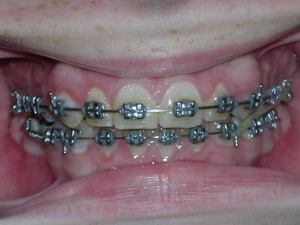

With a combination of braces, expansion and trimming we were able to bring it in. Watch!

Here are the results.